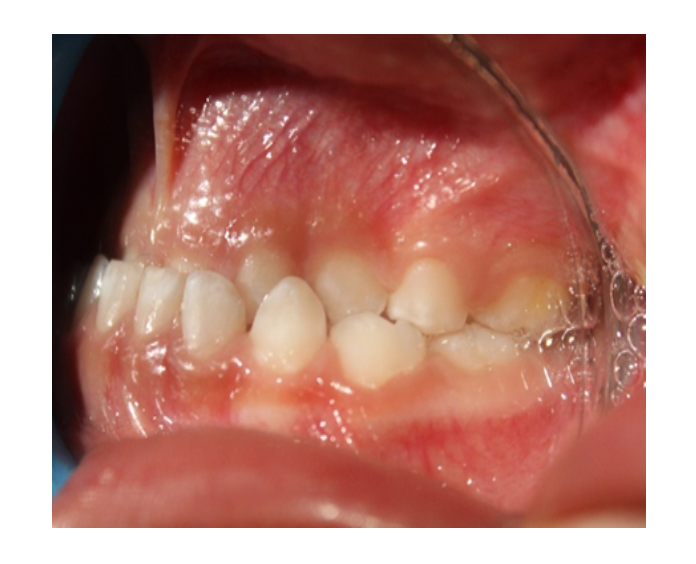

Mordida cruzada posterior bilateral